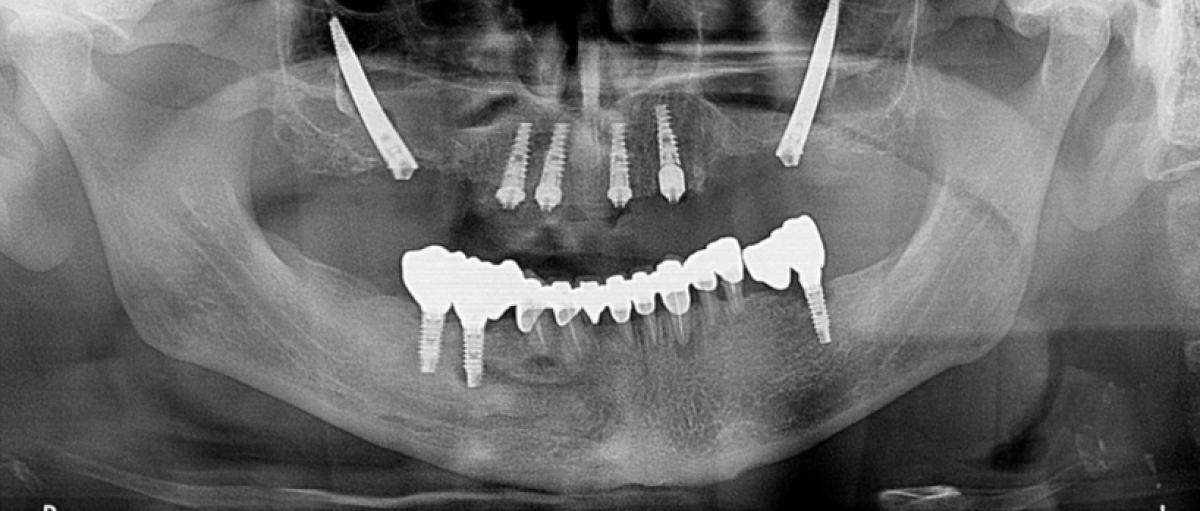

Male 59 year old patient, non smoker, with no evidence of systemic diseases.

The patient presents a superior provisional bridge anchored on three dental pieces 1.2,1.1, 2.3 and on an implant in 2.4.

Additionally, ha has two implants in 1.4 and 1.5 with fractured prosthetic connections that can!t be considered useful anymore.

The dental pieces (1.2, 1.1, 2.3) present a mobility grade III and the implant in 2.4 shows an hori- zontal bone resorption of 4/5mm and previous abscesses.

In the posterior sectors a severe bone atrophy can be observed. FIG 1